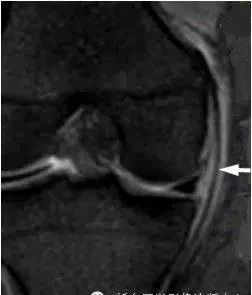

4、桶柄状撕裂

为纵形撕裂伴碎片向内侧移位,这种移位的片段类似于桶的柄,该型撕裂几乎累及半月板的所有部位,常易漏诊,在 MRI 上可以有多种表现,主要为半月板的宽度减小,在通过半月板体部的冠状面上未见到与对侧半月板共同构成的蝶形表现,同时可见到内移的半月板碎片位于髁间窝或交叉韧带旁,可形成双前、后交叉韧带征,这一征象在诊断半月板桶柄状撕裂中有重要意义;